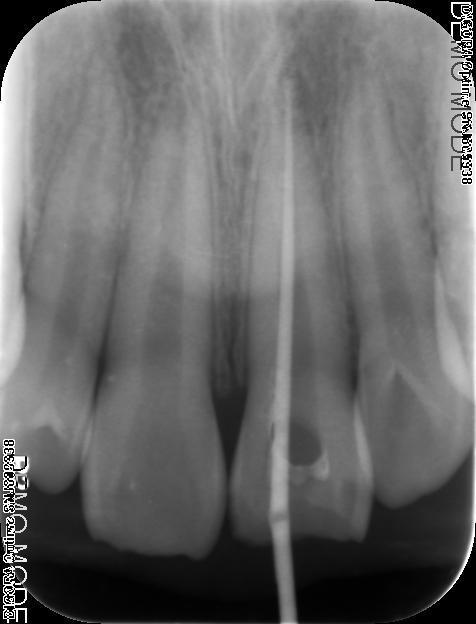

诊断:#21冠折 治疗:#27碧兰麻下开髓,清理髓腔及根管,双氧水和生理盐水交替冲洗,测WL,拍片试尖达工作长度,根管内导入糊剂,侧压充填中下段,热牙胶充填上段,X线示恰填,树脂充填修复。